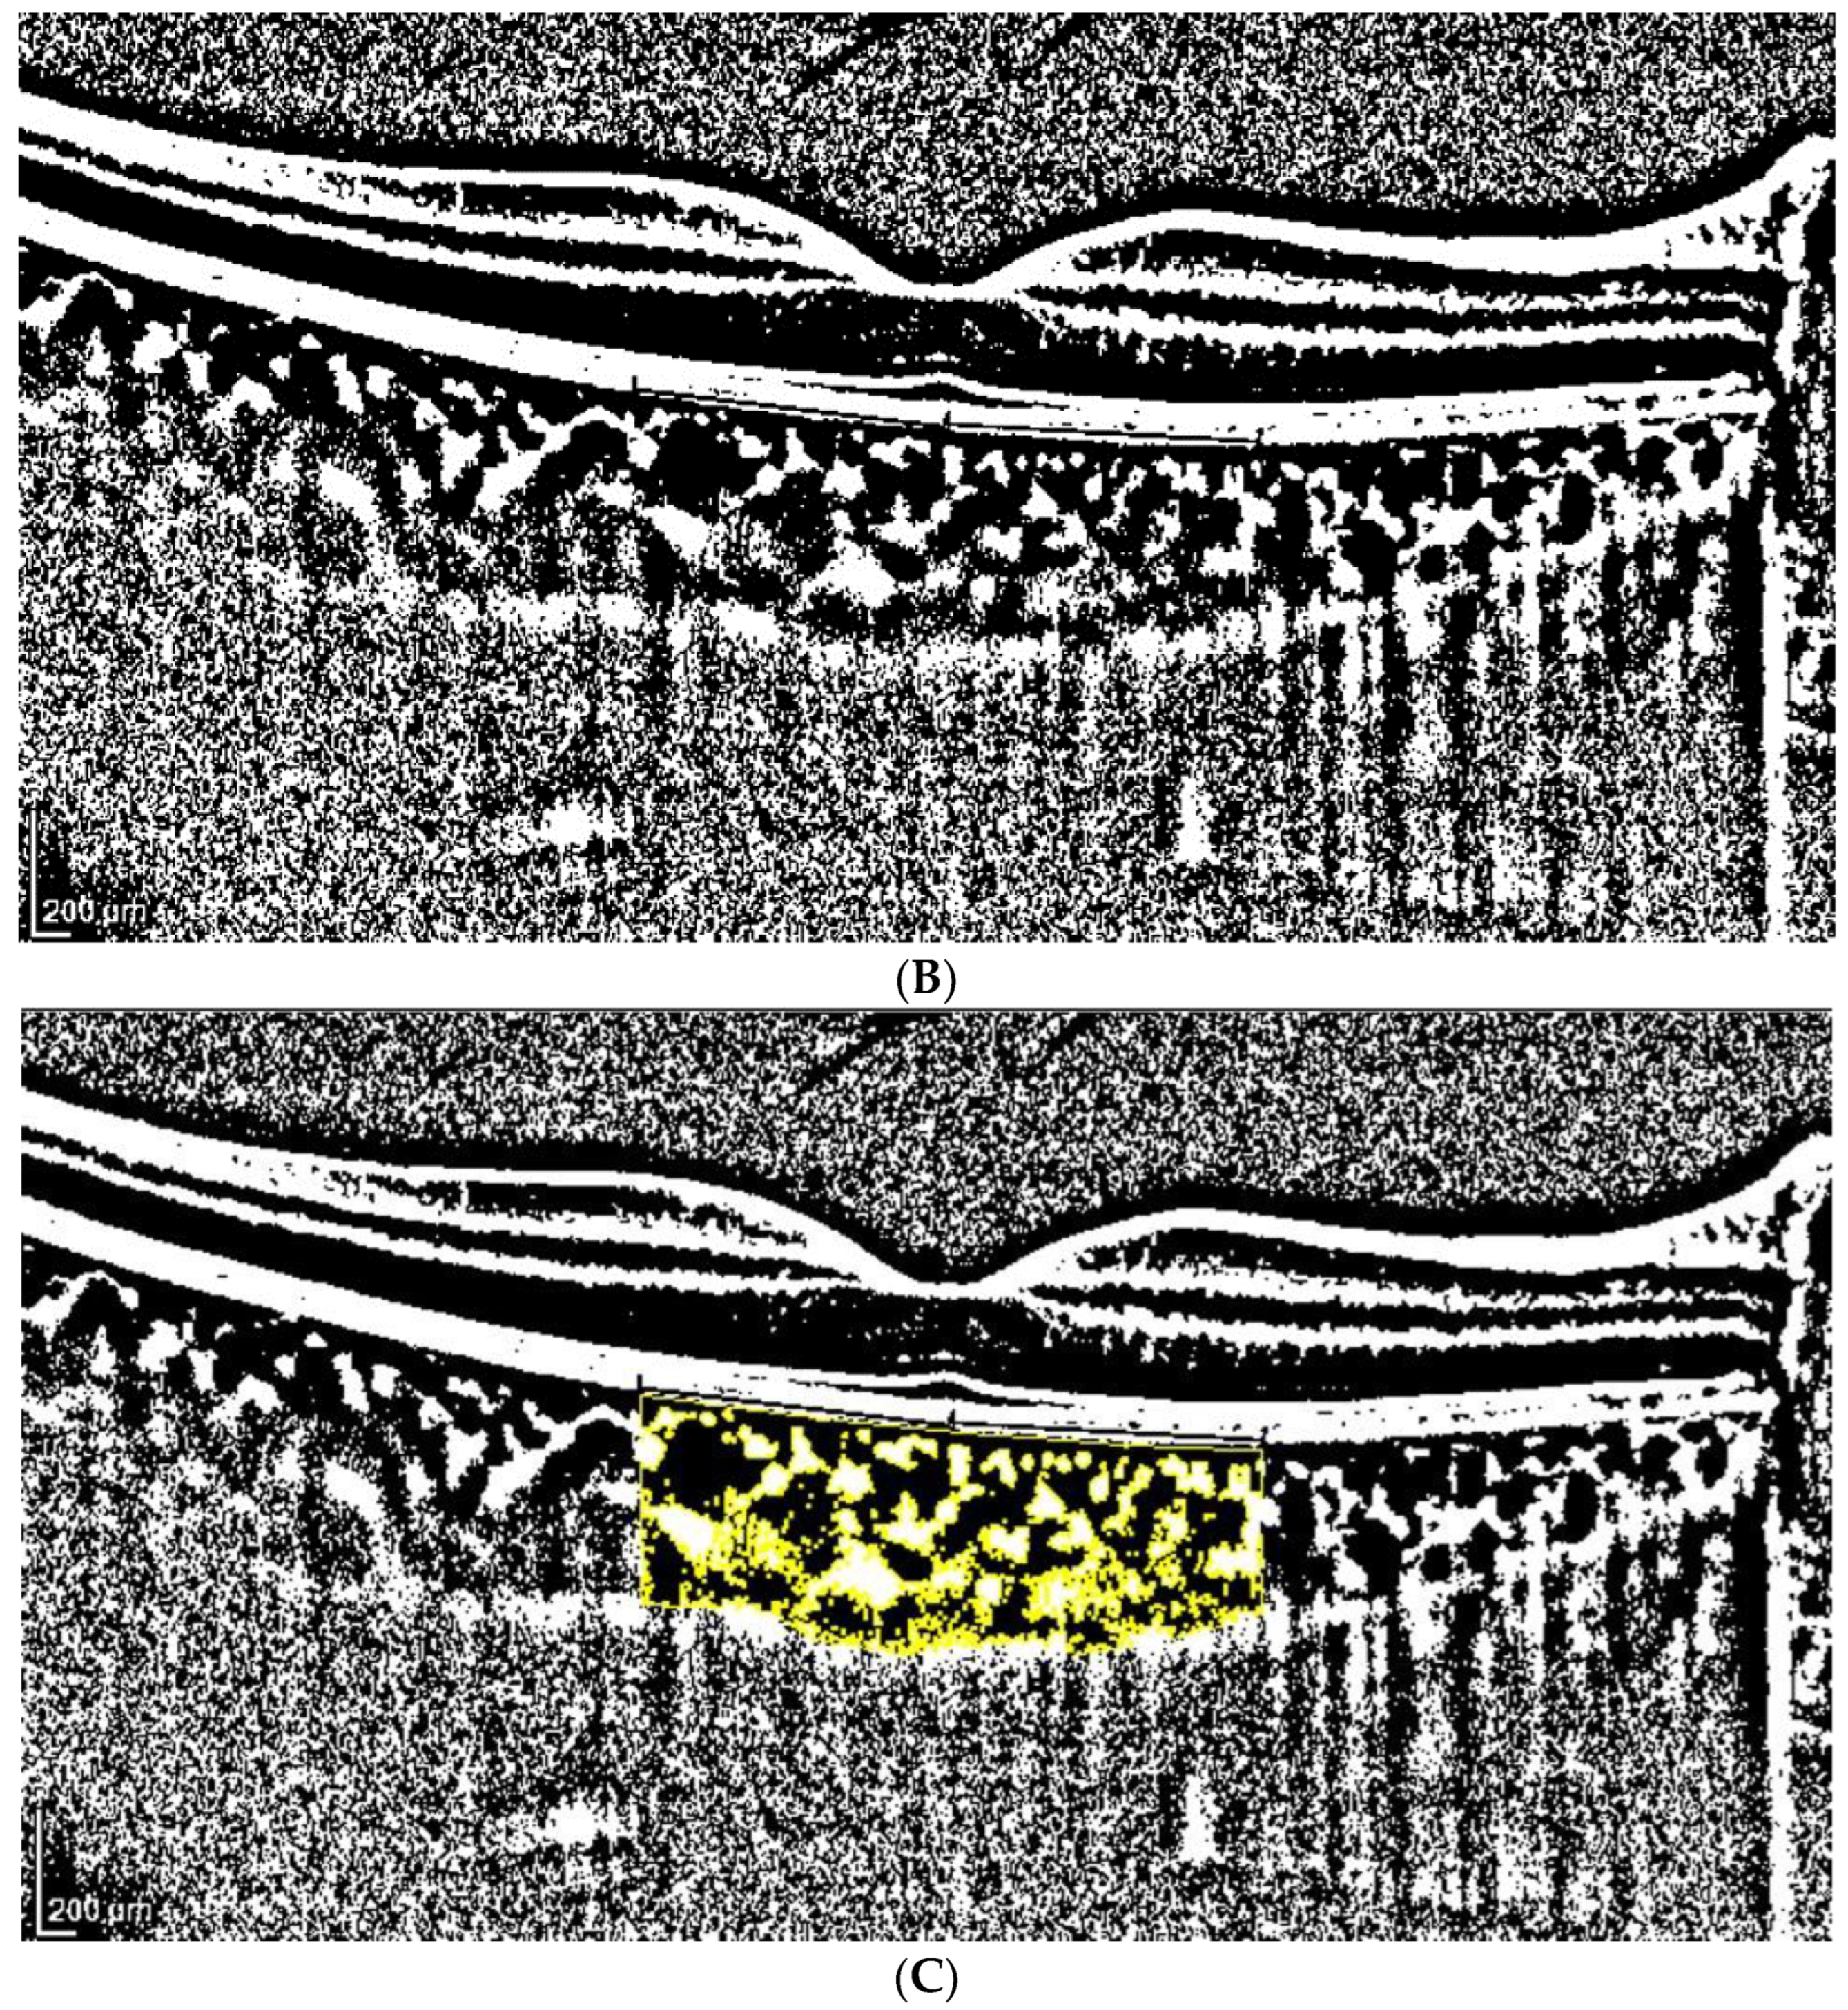

2.3. OCT Analysis

- A classic manual tracking method, manually drawing the lines to limit the choroidal area for each high and low brightness level [2].

- An alternative method, with a fixed area selection independent of the brightness level.